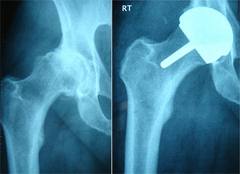

I have helped thousands of patients through my volunteer work and believe me, I am a PATIENT ADVOCATE first and foremost, not a doctor advocate, not a device advocate, but a PATIENT advocate. I want to see successful happy endings for everyone out there. The majority of the failures that I have dealt with had their own surgeons as well as one or two other “specialists” that really did not know much about hip resurfacing, examine their x-rays and tell those patients that the device was placed fine and they must be allergic to the metal or have a metal ion problem. When those patients finally got in touch with me, I sent their x-rays to a group of top surgeons to get their opinions for free. And again, the majority of those patients had poorly placed components. A couple of them had their cups placed so deep that they had holes through their pelvis, no wonder they were in pain after they had surgery!!!

If in fact the BHR device was defective, then the failure rates would be through the roof by now (after 14 years on the market) the way they are with the ASR device (after only about 7 years). After all, the BHR has been around the longest, for 14 years exactly designed the way it still is today as it was 14 years ago, but if you count the first prototypes, it has been over 20 years now. But they are not failing like crazy. They are lower than most THR’s out there. I see WAY more failures of THR’s happening all the time, just go on any THR only support group, you will read stories of patients having their 3rd, 4th or 5th revision in a matter of a few years sometimes. Are they running out and blaming the device? No, most patients just accept that THR’s come with leg length discrepancies and multiple dislocations and end up getting revisions.